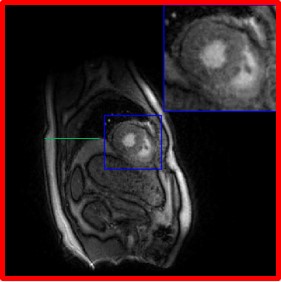

In Fig. 7, we compare the region of interest for SToRM500, SToRM with 150 frames (SToRM150), the proposed method with two different d𝑑d values, the unsupervised Time-DIP approach, and the low-rank algorithm. From Fig. 7, we observe that the proposed scheme can significantly reduce errors in comparison to SToRM150. Additionally, the proposed scheme is able to capture the motion patterns better than Time-DIP, while the low-rank method is unable to capture the motion patterns. From the time profile in Fig. 7, we notice that the proposed scheme is capable of recovering the abrupt change in blood-pool contrast between diastole and systole. This is due to inflow effects associated with gradient echo (GRE) acquisitions. In particular, the blood from regions outside the slice enters the heart, which did not experience any of the former slice-selective excitation pulses; the differences in magnetization of the blood with no magnetization history, and that was within the slice, results in the abrupt change in intensity. We note that some of the competing methods such as Time-DIP and low-rank, blur these details.

Refer to caption

(a) Visual comparisons

(b) Time profiles

Figure 7: Comparisons with the state-of-the-art methods. The first column of (a) corresponds to the reconstructions from 500 frames (similar-to\sim 25s of acquisition time), while the rest of the columns are recovered from 150 frames (similar-to\sim 7.5s of acquisition time). The top row of (a) corresponds to the diastole phase, while the third row is the diastole phase. The second row of (a) is an intermediate one. Fig. (b) corresponds to the time profiles of the reconstructions. We observe that the proposed (d=40𝑑40d=40) reconstructions exhibit less blurring and fewer artifacts when compared to SToRM150 and competing methods.